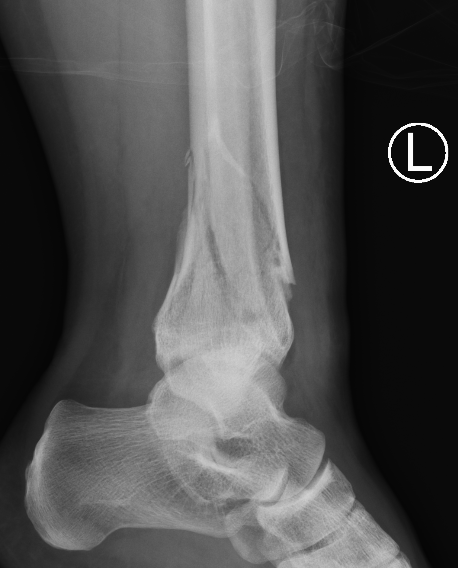

B. Distal Tibial ORIF with plate

Indications

- too distal to nail

- very comminuted / unstable

- intra-articular extension

Technique

1. Consider fixing the fibula

- will aid reduction / avoid malunion

- help control very unstable fractures

2. Anatomically contoured plates

- options of medial plate v anterolateral plate

- medial plate for varus deformity

- anterolateral plate for valgus deformity